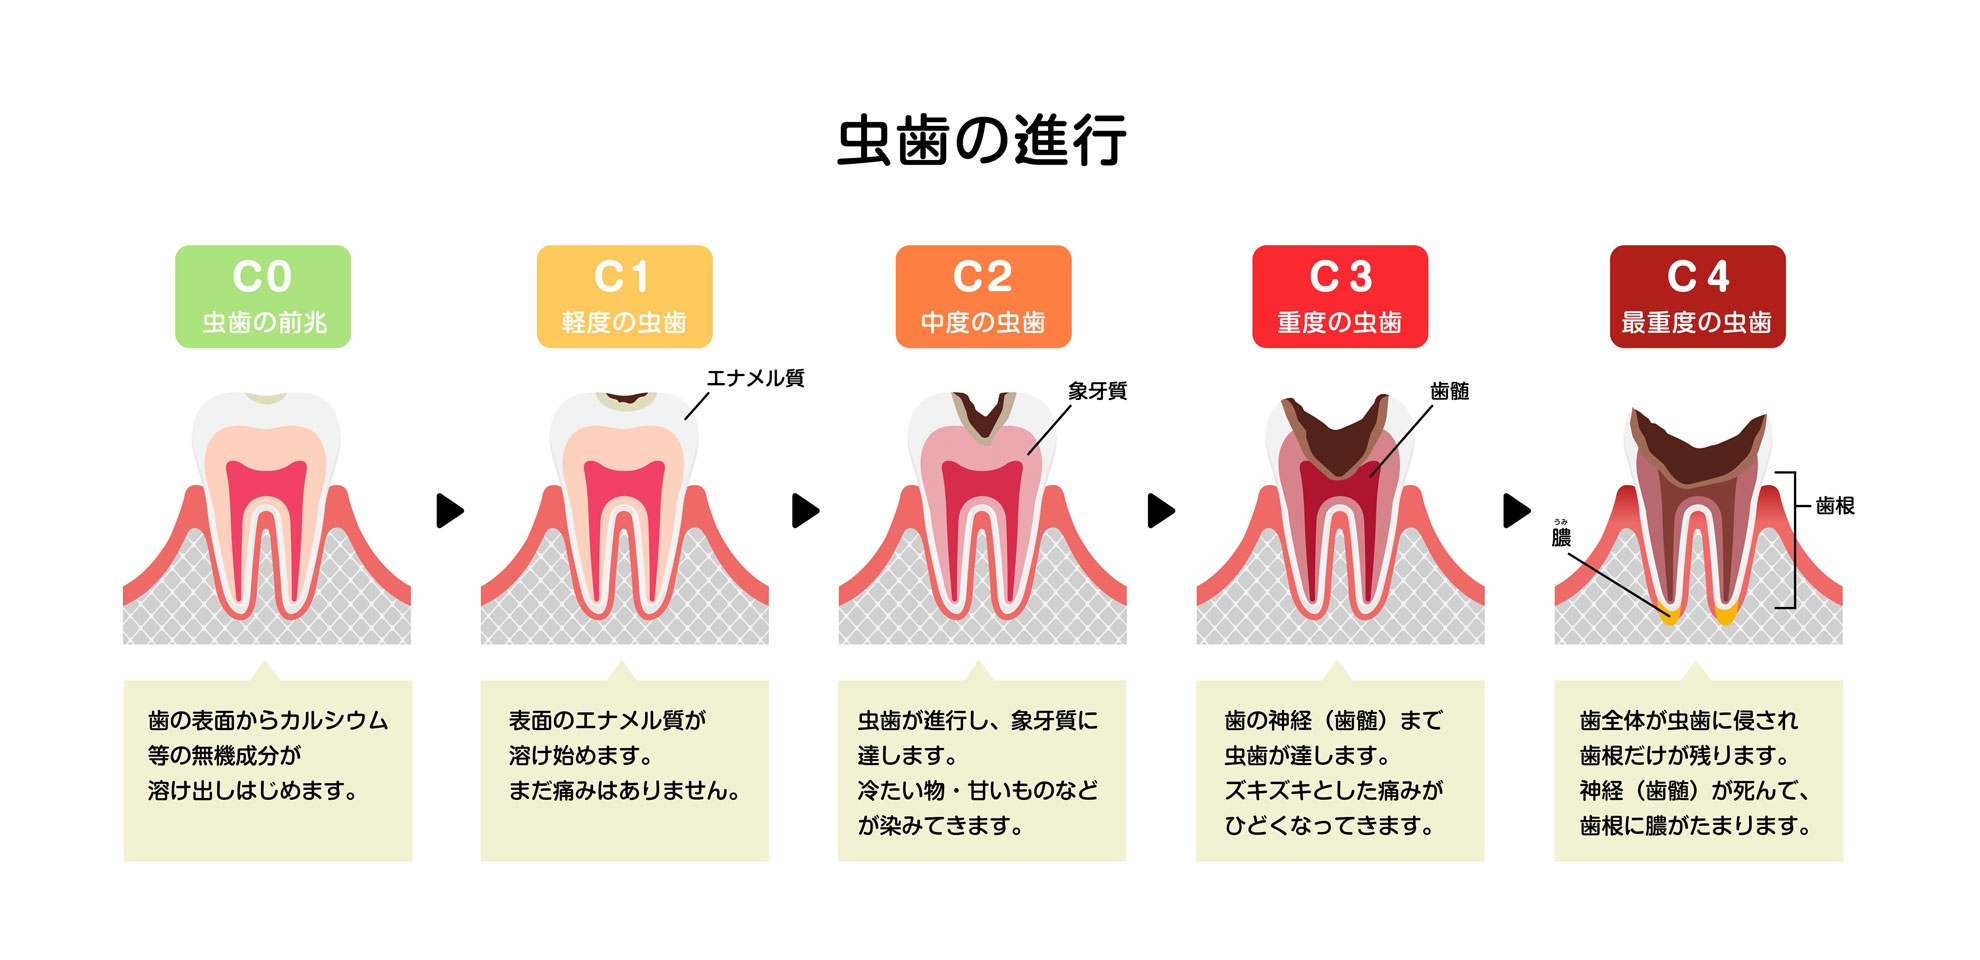

虫歯になったら歯医者さんに行かなければならないのか、と気が重い方もいるのではないでしょうか?. 実は、虫歯は自然治癒を目指せる場合もあるのです。. 自然治癒が可能といっても、虫歯が進行してしまっていれば難しいです。. 自分で治す.. 虫歯を自分で確かめる方法は? 歯医者を受診すべき理由についても. 虫歯の自己診断は可能です。 ただし、セルフチェックには限界もあります。 専門的な知識や技術が必要な場合も多く、正確な診断と適切な治療を行うには、歯医者の受診が不可欠です。 この記事では、虫歯のセルフチェック方法から、虫歯の分類について詳しく解説しています。 歯医者を受診すべき理由、虫歯を放置するリスクについても紹介しているため、ぜひ参考にしてください。 目次. 虫歯かどうかを自分で確かめられる? 虫歯のセルフチェック方法. 痛みがあるか? 変色しているか? 穴が開いていたり形状が変化しているか? 熱いものや冷たいものがしみるか? 医学的な虫歯の進行度合いの分類. CO. C1. C2. C3. C4.